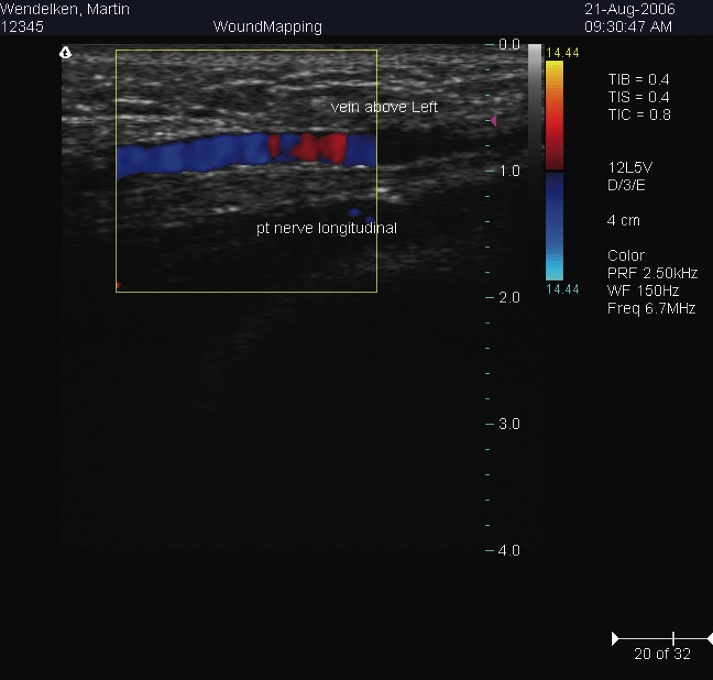

The use of musculoskeletal ultrasound provides podiatric practitioners with non-invasive diagnostic capabilities in the office setting. In addition, this diagnostic tool can also assist with interventional medical techniques for treating a number of pathologic conditions. One may also combine ultrasound with duplex imaging and color Doppler to provide a vascular assessment tool. For this article, we will offer a closer look at the potential of combining musculoskeletal ultrasound with cryosurgery to treat tarsal tunnel syndrome. Before we discuss this new application via an intriguing case study, let us offer a quick review of the advances and evolution of cryotherapy and musculoskeletal ultrasound. For more than 10 years, some podiatric professionals have been using non-invasive diagnostic ultrasound. The schools of podiatric medicine now teach musculoskeletal ultrasonography and have scanners in their radiology departments. This imaging modality enables one to diagnose and discover occult pathology in the musculoskeletal system. In the beginning, clinicians mainly utilized this technology to image the plantar fascia and web space neuromas. Now podiatrists may utilize diagnostic ultrasound to diagnose most soft tissue pathology of the lower extremity. This includes tendons (tendonitis, tendon tears and ruptures), joint capsule and plantar plate tears, soft tissue masses (ganglions), stress fractures and more. In 1998, Wendelken, et. al., patented a method of imaging wounds using diagnostic ultrasound.1 Diagnostic ultrasound has many other uses in podiatry. Combining duplex imaging along with Doppler capability provides a non-invasive method to determine the status of the vascular system of the lower extremity. Color Doppler imaging of the venous system can reveal damage to the valves in veins. Duplex imaging may also show the presence of a thrombus within a vein, which is a potentially life-threatening condition. One may also use this same scanner to detect abnormalities in the arterial system. The measurement of velocities can reveal areas of stenosis within an artery, which, in turn, yield the percentage of closure. Today, skilled podiatrists are now using ultrasound to assist in visualizing invasive treatments. Practitioners can use ultrasound for guidance as it allows for the visualization of trigger point injections. One can use this technique to inject into areas that are difficult to reach anatomically. Ultrasound can also detect and locate foreign bodies. Skilled podiatrists can also perform needle-guided biopsies and guided aspirations using these same guidance techniques. One may also utilize ultrasound to guide plantar fasciotomies and assist in the sclerosing of web space neuromas (using 4% alcohol). These methods of using diagnostic ultrasound have advanced the podiatric profession through technology.

Combining Cryosurgery With Ultrasound: A Guide To Surgical Technique

The procedure involves palpating the posterior tibial artery just proximal to the level of the medial malleolus. We begin by providing anesthesia using a 1 cc syringe of 1% lidocaine with 100,000 dilution of epinephrine. One would inject this solution subcutaneously with a tuberculin syringe 2.5 cm superior to the medial malleolus directly over the posterior tibial artery. We proceed to prep the area in the usual sterile manner with Betadine® and protect the area with a Sound-Seal® thin film dressing (BioVisual Technologies), an FDA-approved protective film dressing for diagnostic ultrasound exams. Cover the area with the sterile dressing and mark the incision site using a sterile pen. A #11 sterile blade provides for a transverse 3 mm full-thickness skin incision. Take care not to violate any deeper structures. (In the aforementioned case study, we performed the procedure in the office under local anesthesia and without tourniquet assistance.) Using a blunt probe, gently penetrate the fascial tissue in the direction of the neurovascular bundle. Use the diagnostic ultrasound machine carefully to help create a tunnel for the cryosurgery probe. Insert the probe into the incision site while under the guidance of the diagnostic ultrasound scanner. We use the HydroStep® Standoff pad to help facilitate compliance over bony prominences such as the medial malleolus. The standoff pad also moves vital structures into specific ultrasound focus zones. The combination of compliance and the shifting of structures deeper into focus zones provides better image quality and resolution. Proceed to introduce the probe into the target area, namely the posterior tibial neurovascular bundle. Since the cryosurgery ice ball ranges in size of 3.5 to 10 mm, depending on environmental conditions, there is no need to dissect the nerve from its adjacent vein and artery. After inserting the probe with pressure directly on the neurovascular bundle, the freezing technique begins. This involves a three-minute freeze cycle, which causes an ice ball formation around the neurovascular bundle. One can directly visualize this process in real time using diagnostic ultrasound imaging. After the initial three-minute freeze, perform a 30-second thaw cycle followed by a second three-minute freeze cycle and 30-second thaw cycle. Generally, the ice ball will surround most of the neurovascular bundle as one can see on the diagnostic ultrasound screen. Once this cycle is completed, withdraw the probe. Dress the incision site with a sterile antibiotic ointment and a gauze compression dressing. No sutures are needed. Our general postoperative course involves no medications and no limitation of activity. The patient is able to shower the following day.